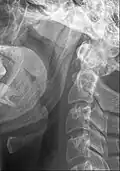

The stylohyoid ligament is a ligament that extends between the hyoid bone, and the temporal styloid process (of the temporal bone of the skull).

It attaches at the lesser horn of the hyoid bone[1][2] inferiorly, and (the apex of[1]) the styloid process of the temporal bone[1][2] superiorly.

The stylohyoid ligament frequently contains a little cartilage in its center, which is sometimes partially ossified in Eagle syndrome.[3]